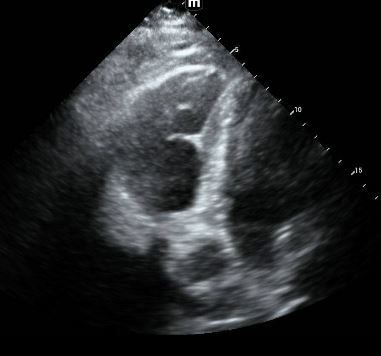

Bedside ultrasound:

4 chamber cardiac ultrasound: RV approximately the same size as LV, with hypokinesis of RV wall except for the RV apex "McConnell's sign"

Bedside 2 point compression ultraosund: +noncompressible R popliteal vein with +echogenic material

- Bedside ultrasound evidence of massive PE may include RV dilation (at least as large the the LV), McConnell's sign (akinesis of the RV wall sparing the apex), or the "D" sign on parasternal short axis, or "clot in transit"